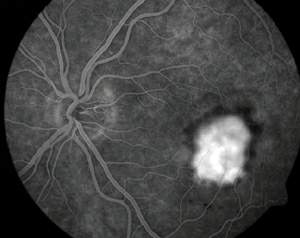

Intermediate age related macular degeneration.jpg

Picture of the fundus showing intermediate age-related macular degeneration.

يأمل الباحثون تطويرَ معالجات جديدة تستطيع إبطاء تقدم التنكس البقعي أو إيقافه. إن المَعْلم المميز للتنكّس البُقْعي هو فقدان الرؤية المركزية، غير أن مظهر الشبكية يختلف على نحو كبير من مريض إلى آخر. وفي معظم الأحيان، يرتبط المرض البقعي عند المسنين ـ الذي يُدعى الاعتلال البقعي المتعلق بالعمر age-related maculopathy (أو اختصارا ARM) ـ بفقدان في خلايا الظهارة RPE. فعندما يُنظر إلى الشبكية عبر منظار العين ophthalmoscope يظهر فقدان تلك الخلايا على شكل باحات غير مصطبغة، أو مصطبغة ولكن على نحو غير منتظم. ويمكن تعرف فقدان خلايا الظهارة RPE على نحو أكثر دقة بالتصوير الفلوروسيني (اللاّصِف) للأوعية fluorescein angiography، وهو تقنية تمكِّن أطباء العيون من رؤية الأوعية الدموية للعين بحقن مركب فلوروسيني في تيار الدم. ففي العين السوية يُرى الصباغ الفلوروسيني بسهولة في أوعية الدم الدقيقة ضمن الشبكية، غير أنه لا يُرى ـ أو يُرى بصعوبة كبيرة ـ في الأوعية المشيمانية الأكثر انتشارا؛ لأن هذه الأوعية تقع خلف الاصطباغ الثقيل للظهارة RPE. أما في عين مصابة بالاعتلال ARM فيظهر الصبغ داخل الدورة المشيمانية في أي باحة فقدت خلايا من الظهارة RPE.

كذلك يستطيع التصوير الفلوروسيني أن يكشف عند نحو %10 من المصابين بالاعتلال ARM عن مشكلة أكثر إنذارا بالسوء: أوعية دموية جديدة نامية من داخل الشبكية أو من تحتها تماما، وهي سيرورة يُطلق عليها اسم تكوّن أوعية جديدة neovascularization. ففي الأحوال العادية تقوم صفحة رقيقة، تكونت خارج الخلايا من پروتينات وسلاسل من عديدات التسكّر، تعرف باسم غشاء بروك(1) Bruch's membrane، بفصل أوعية الدم المشيمانية عن الظهارة RPE. إن أي نمو في الأوعية المشيمانية عبر غشاء بروك هو مدعاة للقلق؛ لأن الأوعية الجديدة تكون عرضة للنزف، وهذا يؤدي في النهاية إلى ظهورٍ غير عكوس لندوب في الشبكية. زد على ذلك أن العيوب في غشاء بروك تتيح للسائل التراكم تحت الظهارة RPE أو بين الشبكية والظهارة RPE، وهذه حالة تُضعف التبادل الغازي والغذائي بين الشبكية ومورد الدم المشيماني.

إن تصوير الأوعية بالفلوروسين تقانة تتيح لأطباء العيون ملاحظة تأثيرات التنكس البقعي بحَقْن (زرق) صبغ فلوروسيني (لاصف) في تيار الدم. وبعد 12 ثانية تماما من الحقن يضيء الصبغ شرايين الشبكية، في حين تبقى الأوردة مظلمة (في اليمين). تظهر البقعة كمنطقة مظلمة بسبب نزيف سبق حدوثه من أوعية جديدة كانت اقتحمت المنطقة المركزية للشبكية. وبعد نصف دقيقة تغدو البقعة ساطعة بسبب الدم المصطبغ الذي رَشَح من الأوعية الجديدة إلى الشبكية (في اليسار).